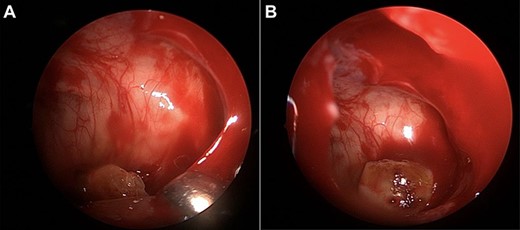

Decongestion and anesthetic were applied to the nose, the right middle turbinate was medialized, and the uncinate was removed using ball tip probe and backbiting forceps in preparation for right maxillary antrostomy. The natural maxillary ostium was enlarged for maxillary antrostomy. Once the antrostomy was complete, the molar was visualized in the posterior, inferior sinus cavity consistent with imaging. It was grasped with Blakesley forceps after several attempts secondary to smooth texture, size and location (Fig. 2). The tooth was pulled into the right nasal cavity but was too large to extract anteriorly through the naris. To prevent trauma to the nasal passageway, the tooth was pushed posteriorly into the nasopharynx and extracted via a transoral approach using a Crowe–Davis retractor and hemostat.

(A, B) intraoperative images of the third molar removal from the maxillary sinus.

Our case successfully utilized an endoscopic approach with maxillary antrostomy for removal of the tooth (Fig. 2A and B). We did remove the tooth from the patient via a final transoral route to prevent injury to the nasal cavity secondary to the size of the nasal cavity, which required pushing the tooth into the nasopharynx. This endoscopic extraction and transoral retrieval is different than prior reports and worked well in a pediatric patient. Providers may consider a transoral approach for final retrieval of the tooth in pediatric patients with narrow nasal cavities.